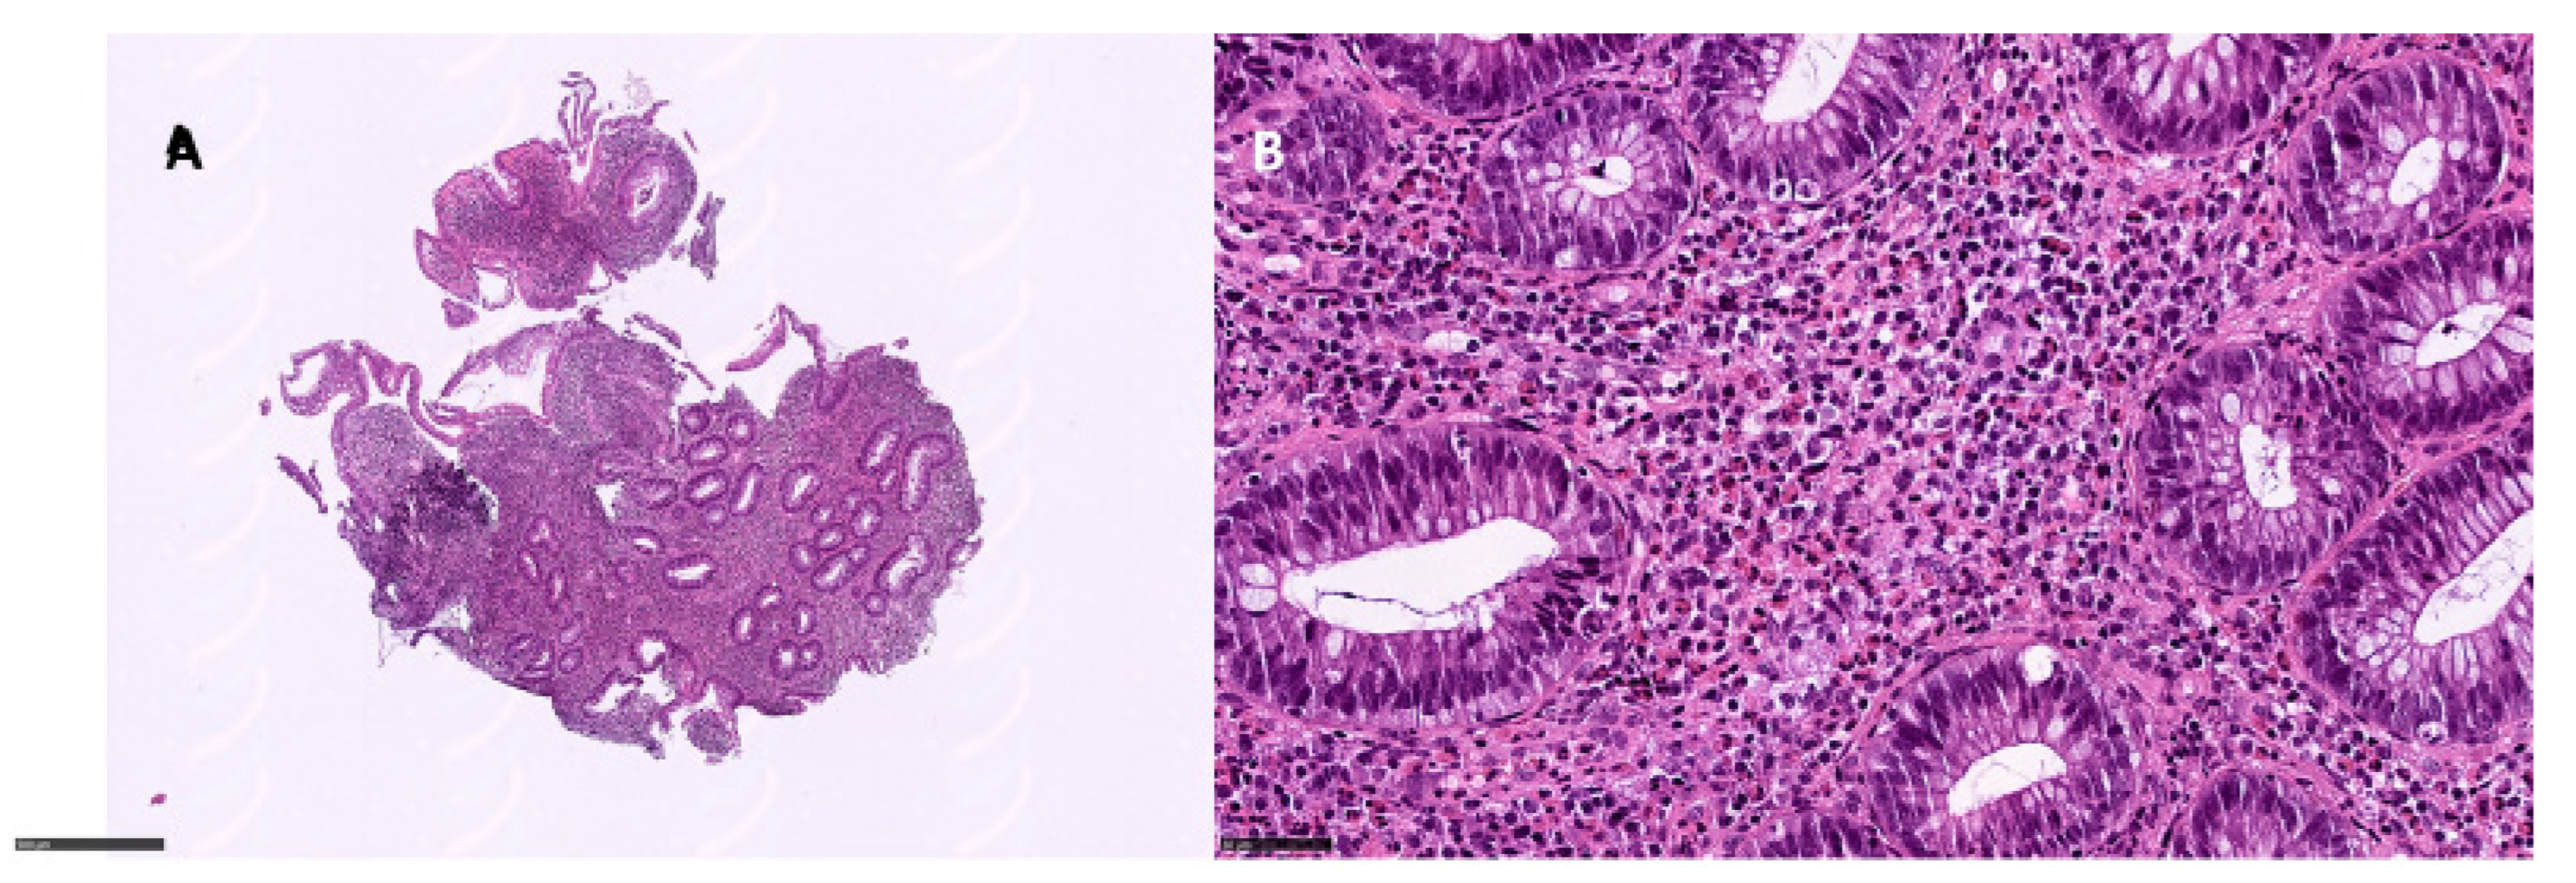

Of the 21 patients, 8 underwent ileo-pancolonoscopy with whole mucosal sampling. Among these, apoptotic combined with ischemic and eosinophilic pattern colitis was observed in two patients, an apoptotic pattern was observed in two patients (Figure 2), apoptotic combined with an IBD pattern was observed in one patient, and apoptotic combined with an ischemic pattern was observed in another patient (Table 3). Eosinophilic pattern colitis was documented in one patient (Figure 3). One patient showed only active colitis. In two patients, the villous blunting of ileal mucosa was documented. CMV was found in two patients.

Figure 2.

Apoptotic pattern colitis: (A) right colon, 9×, showing glandular atrophy and distortion; (B) apoptotic bodies in the glandular element, 25× (hematoxylin and eosin).

Eosinophilic pattern colitis: (A) left colon, 6×, showing a dense inflammatory infiltrate in the lamina propria with middle glandular distortion; (B) eosinophils > 60/HPF in the lamina propria (hematoxylin and eosin).